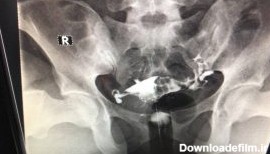

عکس رنگی رحم یا هیستروسالپینگوگرافی به معنای استفاده از اشعه ایکس برای مشاهده رحم و لولههای فالوپ است.

عکس رنگی رحم چیست؟ یک آزمایش اشعه ایکس که برای بررسی رحم و لوله های فالوپ و ناحیه اطراف آنها نگاه می کند و برای بررسی مشکلات ناباروری ممکن است انجام شود.

عکس رنگی رحم یا هیستروسالپنگوگرافی یکی از روش های تشخیصی شیوه ی تصویربرداری با اشعه ایکس است که معمولاً برای بررسی آناتومی رحم و لوله ها انجام میشود. عکس رحم